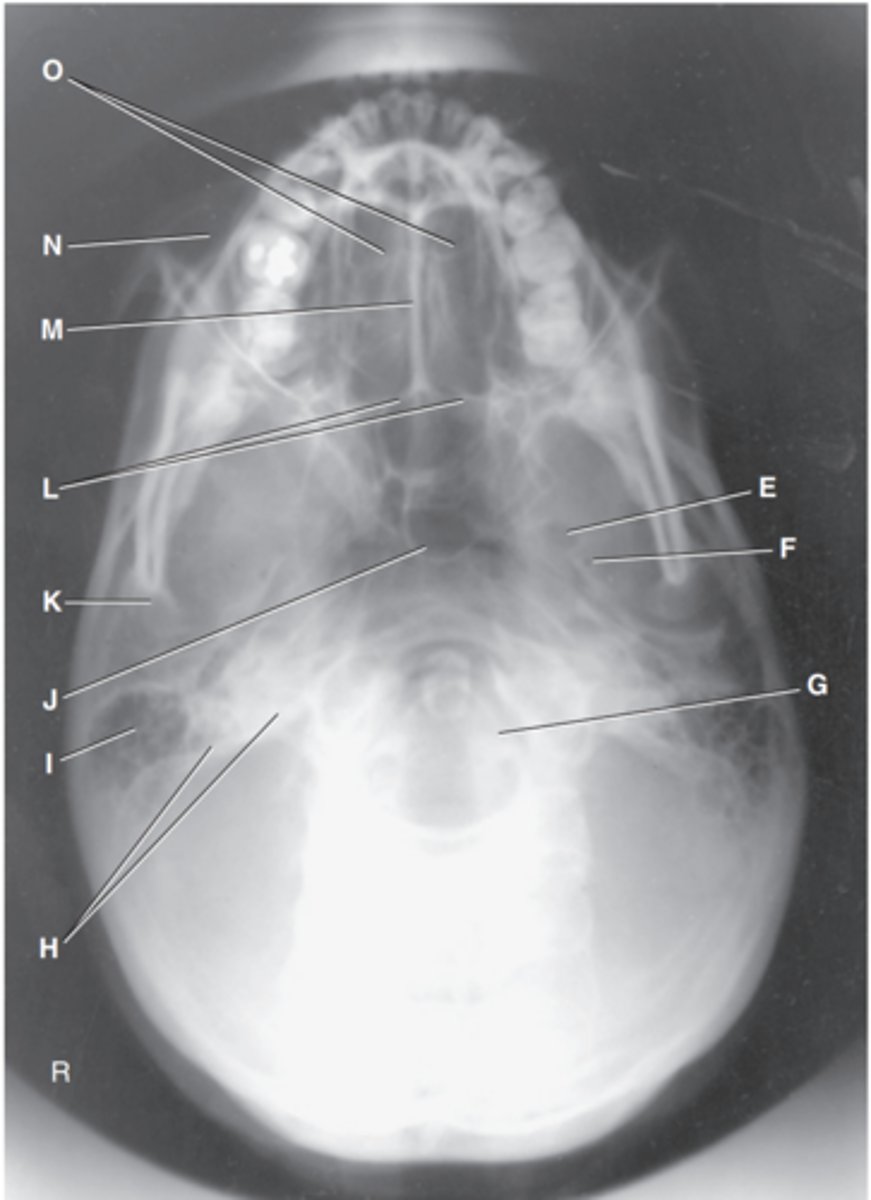

Zygomatic prominence

Label A

Body of maxilla

Label B

Bony nasal septum

Label C

Anterior nasal spine

Label D

Zygomatic arch

Label E

Coronoid process

Label F

Condyle

Label G

Mastoid process of temporal bone

Label H

Angle of mandible

Label I

Foramen magnum

Label J